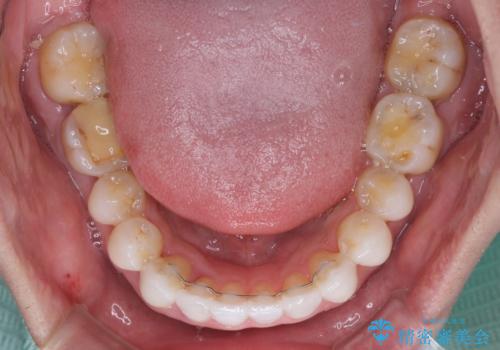

前歯のクロスバイトを改善 インビザラインによる矯正治療

- 前歯のクロスバイトを気にして来院された患者様です。

デコボコやクロスバイトが散見されたため、IPR(歯と歯の間を削る)によってスペースを獲得できるように設計し、インビザラインにより治療を行うこととしました。

今回は、ワイヤー装置を併用することなく治療を行い、トラブルなく、満足のいく歯列に整えることができました。

矯正治療の途中でホームホワイトニングを併用され、術前とは見違えるほどきれいな口元となりました。